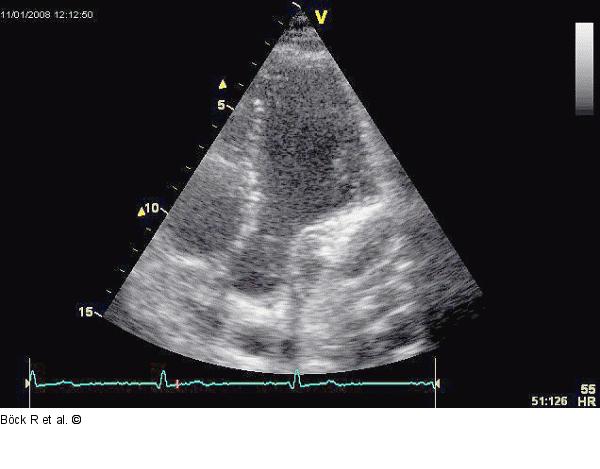

Abbildung 4: Sinus coronarius Kaudal angulierter Vierkammerblick nach Kontrastmittelgabe. |

Kaudal angulierter Vierkammerblick nach Kontrastmittelgabe. |